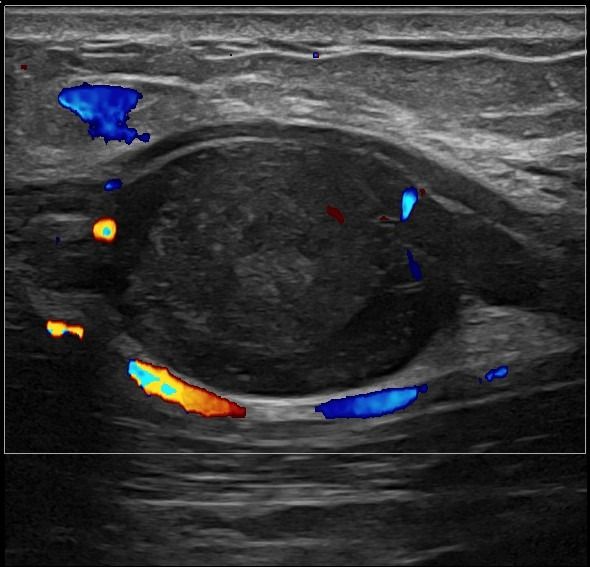

- Entrapment Syndromes (carpal tunnel syndrome, cubital tunnel syndrome, tarsal tunnel syndrome, meralgia paresthetica)

- Focal Lesions (tumors, neuromas)